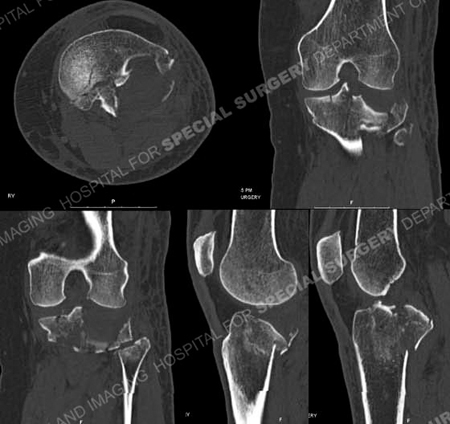

CT scan images further delineating the fracture pattern and depressed bone fragment.

Schatzker II tibial plateau fracture

A 61-year old female was hiking in the mountains when she slipped and fell onto her left lower extremity. She was taken to a local hospital and radiographs revealed a left-sided Schatzker II tibial plateau fracture (split with depressed fragment) and she was referred to Dr. David L. Helfet at the Orthopedic Trauma Service at Hospital for Special Surgery one day following her injury for definitive treatment. Open reduction and internal fixation (ORIF) was performed and included elevation of the depressed fragment, placement of bone graft, reduction of the articular surface and metaphyseal extension and placement of a proximal tibia locking plate and screws. She returned for regular follow-up and healed uneventfully. At the time of her latest follow-up visit, 7 months following fracture surgery, she has excellent radiographic and clinical results including a healed tibial plateau fracture in excellent alignment, maintenance of fixation and knee joint space, complete pain resolution, full range of motion and a return to pre-injury activities.